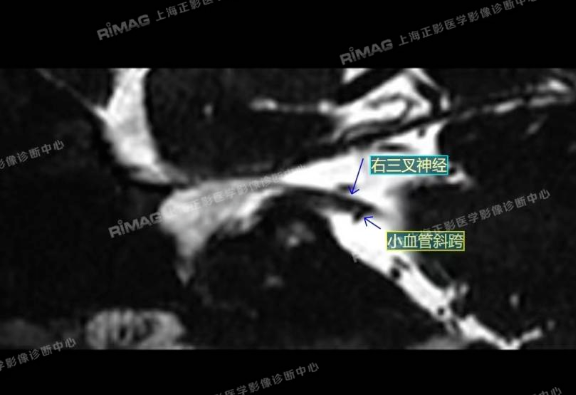

影像表现:右侧三叉神经根部外下方见小血管斜跨,与三叉神经分界不清;左侧未见明显异常(对照)。

MRTA:磁共振体层成像脑血管显影术,可清楚显示三叉神经与周围血管空间关系,为术前筛选、术中探查责任血管,提高手术疗效等提供了可靠的影像学依据。

在上述显示的影像图上,血管与神经的纠缠一目了然。这正是现代影像学的魅力——它不仅是“拍片子”,更是“讲故事”,是把病人多年的痛苦,转化为可视化的医学证据。